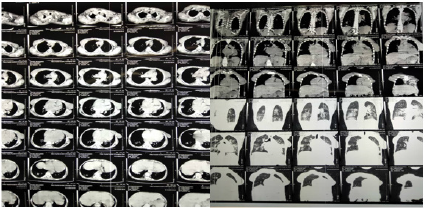

Full septic screening was done with no isolated organism, urine culture showed no growth, three-time negative blood culture and negative gene Xpert for tuberculosis. Erythrocyte sedimentation rate (ESR): 70 mm/hr (normal ref 1–20 mm/hr), C reactive protein: 22 mg/L (Normal ref: below 3.0 mg/L).Hemoglobin level: 11.7 ( normal ref: 12-16 g/dl), total white blood cells 4.3 ( normal: 4-10). CT Chest was done which showed bilateral ground glass opacity (Figure 2). And a diagnosis of COVID 19 was highly suspicious, Sputum and nasopharyngeal swab collected on day 14 after admission.